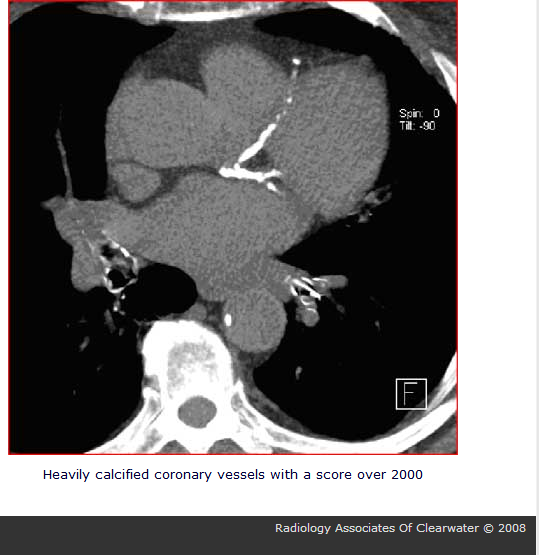

Image

Fig. 8.1 Hybrid methods: myocardial perfusion SPECT + CT + CTCA

a: left ventricle longitudinal section image on myocardial perfusion SPECT

b: left ventricle longitudinal section image identically on CT

c: SPECT + CT fusion image (function + morphology)

d: myocardial perfusion SPECT + CTCA (CT Coronary Angiography) 3D fusion

Normal conditions.

Based on tissue density data provided by the CT, SPECT data can be corrected in order to estimate actual myocardial perfusion activity (attenuation correction, scattering, depth dependent correction) and in case of PET even quantitative perfusion data can be calculated (ml/gr tissue/minute)

Coronary Calcium Score (CCS) assessment is possible with the CT scan

3D reconstruction of CTCA and perfusion conditions facilitates combined evaluation of the actual coronary status and perfusion in the region of a specific vessel.